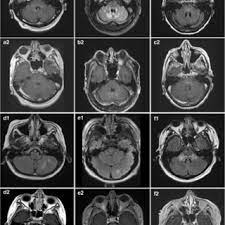

Clippers An Increasingly Recognized Chronic Inflammatory Central Nervous System Disorder The American Journal Of Medicine

Moss m.b., m.s.albert, n.butters et al. Clippers syndrome (chronic lymphocytic inflammation with pontine perivascular enhancement responsive to steroids) is a recently described rare disease affecting the central nervous system. Chronic lymphocytic inflammation with pontine perivascular enhancement responsive to steroids. Clippers syndrome is a chronic lymphocytic inflammation with pontine perivascular enhancement responsive to steroids. Erste fälle wurden in den usa diagnostiziert.